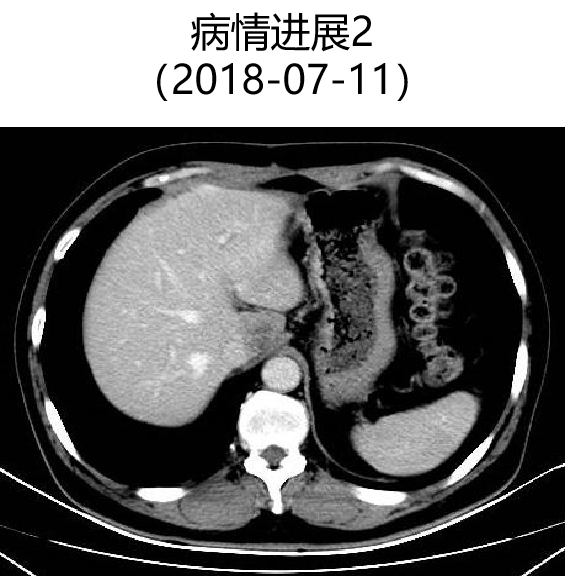

二 病例分享 专家简介 01 基本情况 患者:汪XX,男,63岁。身高 165cm;体重 65kg;体表面积 1.70m2;ECOG 1分。 主诉:反复解黏液血便3天。 对磁共振造影剂过敏,无食物、其他药物过敏史。既往史、个人史、婚育史、家族史均无特殊,无吸烟、饮酒史。 02 初诊病史 现病史:患者2017年3月初无明显诱因下解黏液血便,量中等,为鲜血,反复发作,无恶心、呕血、黑便、腹痛、腹泻、里急后重等不适。遂于2017年3月初就诊我院。 胸、腹、盆腔CT平扫+增强:乙状结肠肠壁明显增厚,肠腔狭窄,增强期强化明显;肝脏多发低密度病灶,增强期不规则强化,考虑乙状结肠癌伴肝脏多发转移。 03 治疗方案 【一线治疗】 2017-06-22 西妥昔单抗+FOLFIRI* Q2W×3 西妥昔单抗 900mg ivgtt D1; 5-氟尿嘧啶 0.6g iv D1,3.5g civ 48h; 亚叶酸钙 0.6g ivgtt D1; 伊立替康 280mg ivgtt D1。 第1疗程结束后黏液血便较前消失,过程顺利,耐受良好,无皮疹、腹泻等不良反应,治疗10疗程,疾病进展。 疗效评估-影像学(部分缓解,PR)。 2017-07-15 乙状结肠癌切除术* 手术记录:肿瘤位于乙状结肠,大小约4cm×3cm,未突破浆膜层,病灶周围可及数个稍肿大淋巴结,未及盆底种植结节。 手术过程顺利,术后恢复良好。 术后病理:(乙状结肠)中分化腺癌,浸润肠壁浆膜下层,两切缘阴性,未见脉管癌栓及神经束侵犯,LN 2/18(+) 2017-08-20 肝转移瘤切除术* 手术记录:肝脏肿瘤位于肝右叶,大小分别约2cm×1.5cm,1cm×1.2cm,其余肝表面未见异常结节,腹腔无腹水、无粘连。 手术过程顺利,术后恢复良好。 术后病理:(肝右叶病灶)中分化腺癌,结合临床病史,符合乙状结肠癌肝转移,肝组织切缘未见癌。 疗效评估-影像学(NED)。 2017-11-06 西妥昔单抗+FOLFIRI* Q2W×3 西妥昔单抗 900mg ivgtt D1; 5-氟尿嘧啶 0.6g iv D1,3.5g civ 48h; 亚叶酸钙 0.6g ivgtt D1; 伊立替康 280mg ivgtt D1; 过程顺利,无皮疹、腹泻等不良反应。每疗程后均予PEG-CSF预防性升白,耐受良好。 疗效评估-影像学(病情进展,PD1)。 胸、腹、盆腔CT平扫+增强:肝左外叶低密度灶,增强期不规则强化,结合病史,考虑结肠癌肝转移,余未见明显异常。 【二线治疗】 2018-03-06 肝左外叶肿瘤切除术* 术中探查见:肿瘤位于肝左外叶,质硬,边界不清,余肝脏表面未见异常结节灶,腹盆腔无腹水。 手术过程顺利,术后恢复良好。 术后病理示:(肝左叶)中分化腺癌,结合临床病史,符合结肠腺癌肝转移。 2018-04至2018-07 卡培他滨+奥沙利铂* Q3W×5 卡培他滨 1.5g BID D1-14; 奥沙利铂 200mg ivgtt D1。 过程顺利、耐受良好,无腹泻、神经毒性等不良反应。 疗效评估-影像学(病情进展,PD2)。 胸、腹、盆腔CT平扫+增强:肝尾状叶结节状异常密度灶,增强期不规则强化,结合病史,考虑结肠癌肝转移,余未见明显异常。 2018-07至2020-04 贝伐珠单抗+卡培他滨* Q3W×21 贝伐珠单抗 500mg ivgtt D1; 卡培他滨 1.5g BID D1-14。 过程顺利、耐受良好,期间曾出现II度腹泻,对症治疗后可恢复正常。无血压升高、出血、蛋白尿、手足皮肤反应。 疗效评估-影像学(最佳疗效,PR)。 疗效评估-影像学(病情进展,PD3)。 腹腔镜肝尾状叶切除术+腹腔粘连松解术* 术中探查见:肿瘤位于肝尾状叶,质硬,边界不清,余肝脏表面未见异常结节灶,腹盆腔无腹水。 手术过程顺利,术后恢复良好。 术后病理示:(肝尾状叶)中分化腺癌,结合临床病史,符合结肠腺癌肝转移。 2020-06至2021-09 贝伐珠单抗+卡培他滨* Q3W×16 贝伐珠单抗 500mg ivgtt D1; 卡培他滨 1.5g BID D1-14。 过程顺利、耐受良好,期间曾出现II度腹泻,对症治疗后可恢复正常。无血压升高、出血、蛋白尿、手足皮肤反应。 疗效评估-影像学(NED)。 疗效评估-影像学(NED)。 【三线治疗】 2021-12-16 西妥昔单抗+TAS-102* Q3-4W×2 西妥昔单抗 900mg ivgtt D1; TAS-102 60mg BID D1-5,8-12。 过程顺利、耐受稍差,期间出现II度骨髓抑制(三系减少),对症治疗后可恢复正常。无皮疹、输液反应等。 疗效评估-影像学(部分缓解,PR)。 04 治疗小结